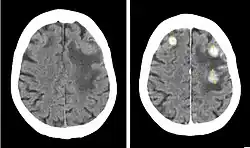

Iopentol (trade name Imagopaque) is a pharmaceutical drug that was used as a radiocontrast agent for X-ray imaging in Europe.[1]

Uses included arteriography (imaging of arteries), venography (imaging of the veins) and CT scan enhancement, urography (imaging of the urinary system), arthrography (imaging of the joints), endoscopic retrograde cholangiopancreatography (ERCP; imaging of bile and pancreatic duct), hysterosalpingography (imaging of the uterus and fallopian tubes), and gastrointestinal studies.[1]

Iopentol is an iodine-containing, water-soluble radiocontrast agent. The iodine atoms readily absorb X-rays, resulting in a higher contrast of X-ray images. It has a low osmolality, meaning that the solution has a relatively low concentration of molecules; this is usually associated with fewer adverse effects than high-osmolality contrast agents.[1][2]

A phase III clinical trial concluded that iopentol produces images of a similarly high quality as iohexol, and that it is equally well tolerated by patients.[1]